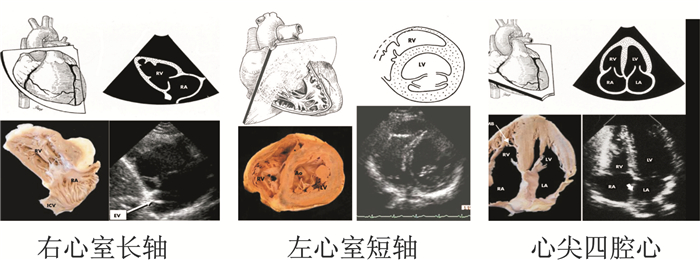

2.3 右心衰竭的病理机制右心室的功能是在不引起肺动脉压升高和不影响左心室充盈的前提下尽可能确保更多的系统静脉血回到右心,并将每次心搏来自周身的血液传输给肺循环。每次回心血量并非完全一致,右心室充盈压及肺动脉压力会在最小限度内有一定的波动。

当肺血管储备功能受损时右心室的射血能力才会表现出下降。如急性肺栓塞会引起右心室流出道阻力急剧增加,进而导致右心室扩张、心室之间相关作用导致左心室舒张顺应性迅速下降,最终导致心源性休克甚至死亡。体循环低血压进一步引起右侧冠状动脉灌注压下降、右心室室壁张力的增加、心肌做功以及氧耗的增加,从而导致右心室功能恶化。上述的病理变化直接提示了急性肺栓塞患者或者各种原因导致的急性肺动脉高压患者,出现急剧性血压下降或者冠脉灌注不足。慢性肺动脉高压导致的右心室肥大主要是与肺循环阻力升高相适应的结果。随着病情进一步进展,右心室进行性肥大与持续增加的右心房压力增加、左心室充盈进行性受限、患者活动耐力进行性下降相关。很显然解除右心室流出道梗阻、降低肺循环阻力是最大化降低右心室扩张、缓解右心室衰竭关键的治疗措施。当肺动脉压力增高超过右心室收缩能力的极限时或者合并出现了肺血管闭塞性改变时,终末期的肺源性心脏病就不可避免了。

基于Buckberg[12]研究显示,右心室收缩舒张功能的实现主要是由室间隔运动而非右心室游离壁心肌来完成,一半以上的右心室收缩力是基于左心室收缩后产生的。所以,急性肺心病通常会通过改善左心室收缩功能来维持冠脉灌注压或者降低肺动脉压力。血管收缩药物主要用来维持右心室收缩期冠脉灌注压高于肺动脉压的需要[10]。需要强调的是,右心室后负荷增加是限制右心室射血的主要原因,所以致力于最大程度降低肺循环阻力、提高肺血管的顺应性才可能会从根本的获益。右心衰竭时表现的病生理变化见图 4。

| 图 4 右心衰竭的病生理变化 |